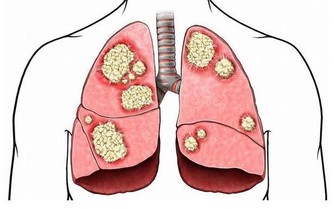

有兩條膀胱經通路在此經過,此處聚毒最多。

若聚毒難散,體內必生瘀積腫物;若此處常通,則癌癥不生,惡疾難成。

膀胱經預防和主治的疾病:呼吸系統:感冒、發燒、哮喘、肺炎;